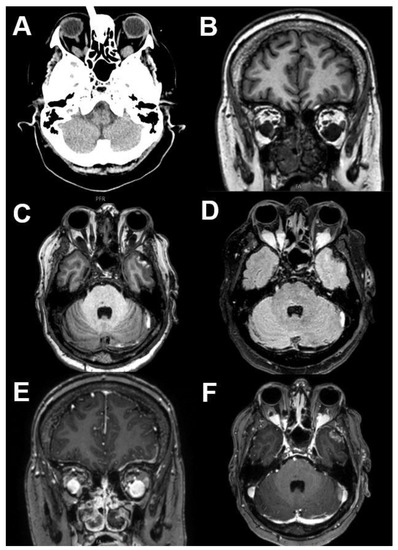

3.1.1. Retinoblastoma

3.1.2. Uveal Melanoma